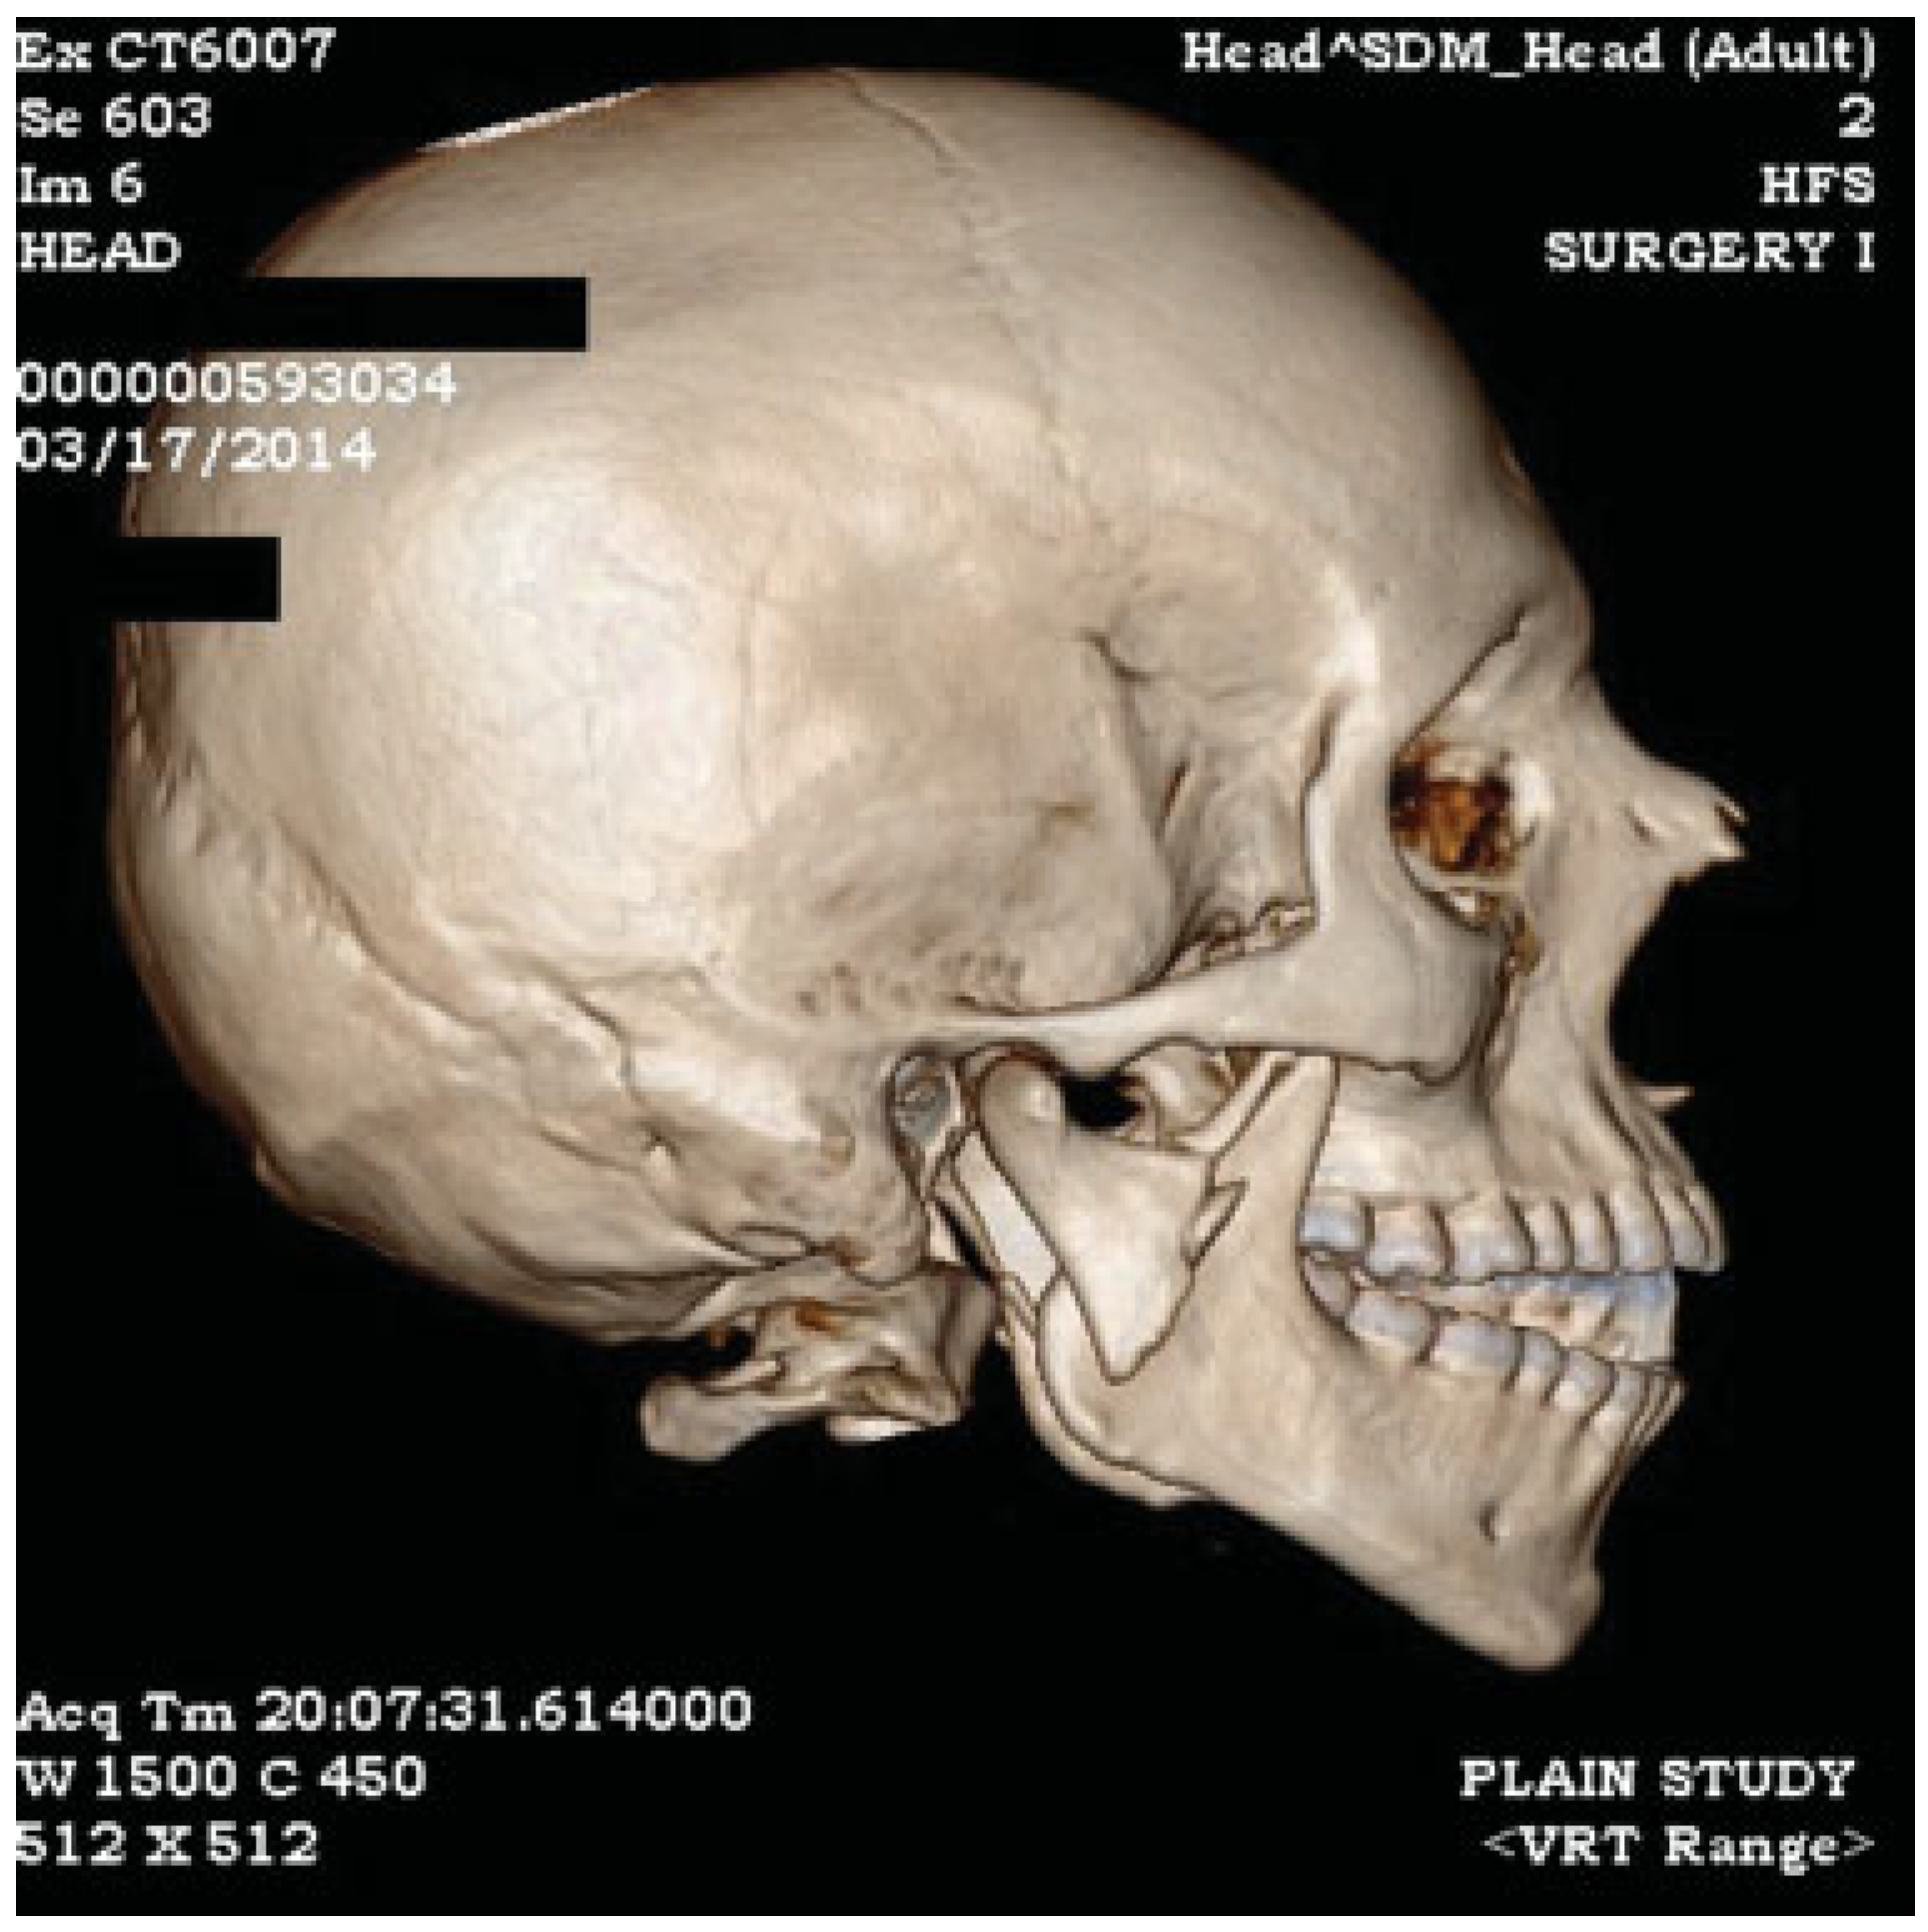

Figure 2.

3D reconstruction image showing laterally displaced condyle with shortening of posterior ramal height with premature occlusion of posterior teeth resulting in anterior open bite.